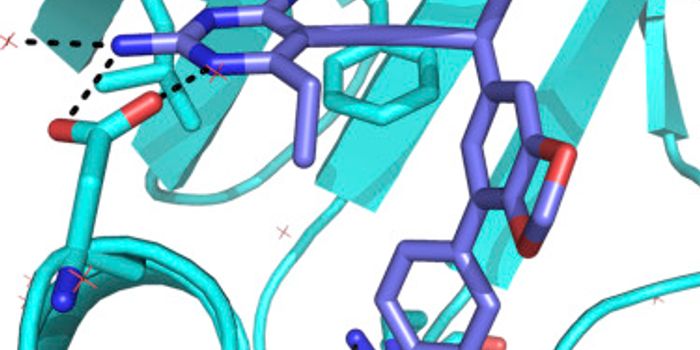

FEB 20, 2019Drug Discovery & DevelopmentResearchers at the Technical University of Denmark are working towards finding new methods for battling antibiotic resis ...